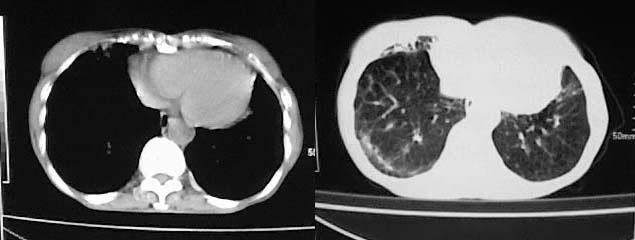

以下是引用有风的日子在2008-5-2 12:13:00的发言:[br][emb10][br][br]肺ca?有病理支持吗?[br][br]我看更象是肺tb并支扩、间质性肺炎。最好拿个病理结果来,不然这点影像资料诊断肺ca是难以服人的![br][br]至于主动脉瘤的诊断问题,国外认为≥4.0cm就可诊断了,国内对此诊断标准更为严格。患者升主动脉明显增粗,即>4cm。你诊断个升主动脉扩张并不为过!

以下是引用zjzjr在2008-5-2 14:39:00的发言:[br]支持双侧继发型肺结核,左侧胸膜肥厚,慢性支气管炎伴间质纤维化.